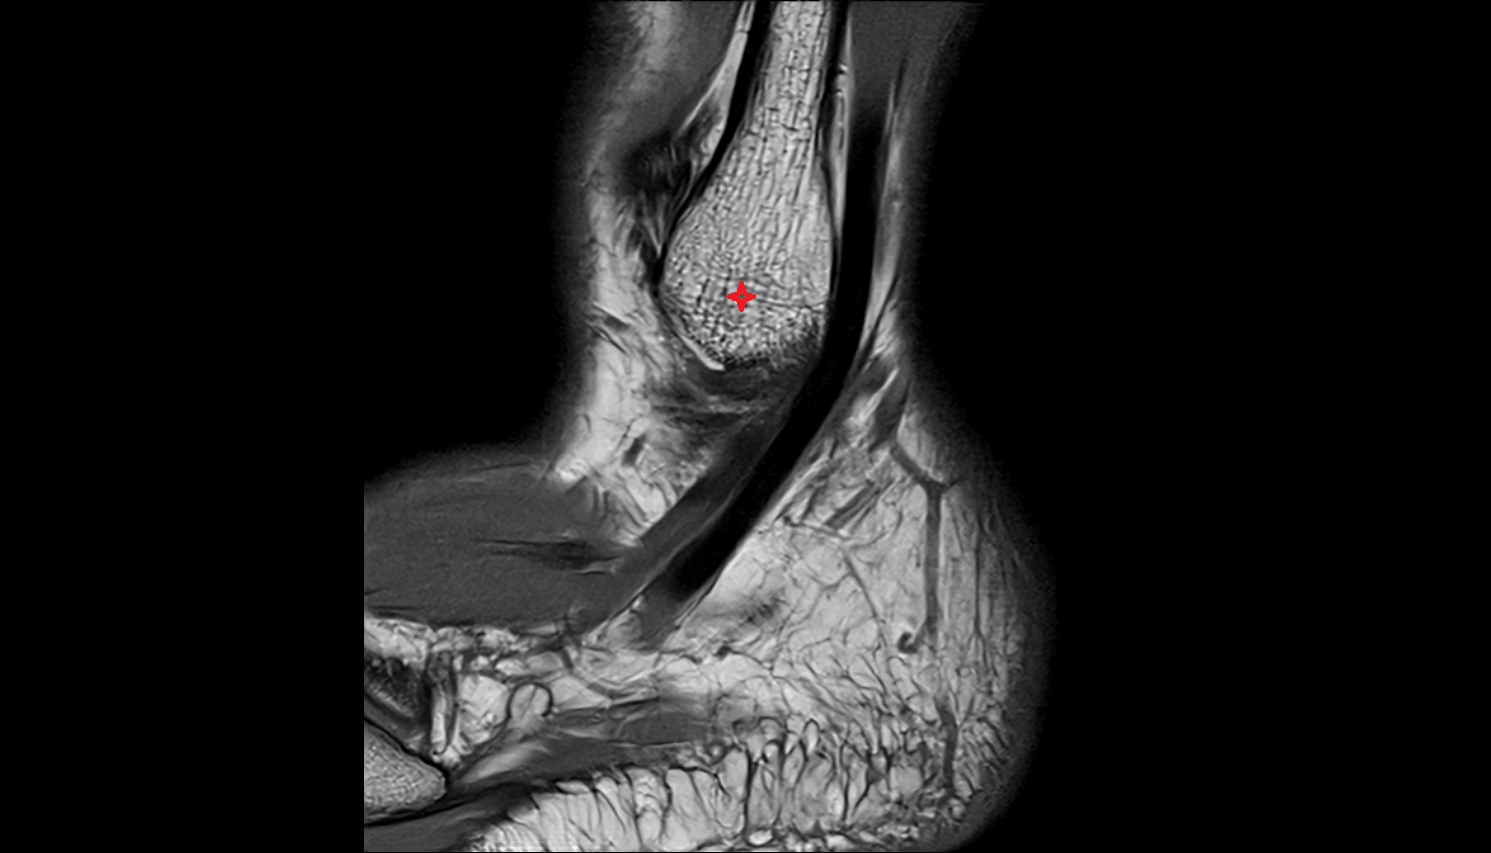

- Talus

- Head of talus

- Body of talus

- Neck of talus

- Calcaneus

- Ankle joint

- Talocalcaneal joint